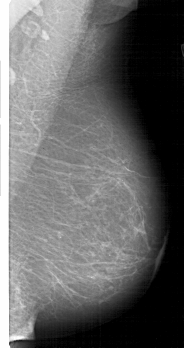

A_1812_1.RIGHT_MLO

RIGHT_MLO LINES 5206 PIXELS_PER_LINE 2746 BITS_PER_PIXEL 12 RESOLUTION 43.5 NON_OVERLAY